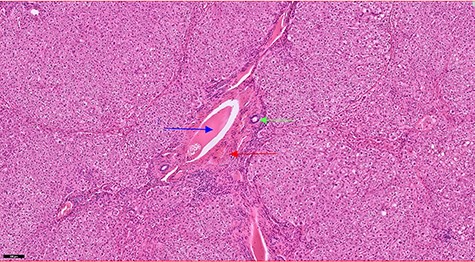

The operation was performed under general anaesthesia with the patient intubated using a double-lumen endotracheal tube. A 4 cm incision was made in the right sixth intercostal space in order to locate the mass. After the insertion of a 10 mm 30-degree thoracoscope, a rounded smooth-surfaced, broad necked mass attached to the right hemidiaphragm was visualized (Fig. 3). The decision to open the diaphragm was made. Further dissection and exploration with an energy device revealed that the mass which was bounded superiorly in the form of a pouch by the diaphragm and had arisen from the liver (Fig. 4). The mass was completely resected with HARMONIC ACE® +7 (Ethicon) after consulting with the hepatobiliary surgeon who felt there was a clear cleavage plane between the mass and liver. The exposed area of liver was covered with Floseal®(Baxter) and TachoSil®(Takeda). The diaphragmatic defect (Fig. 5) was closed in a single layer with 10 simple interrupted silk sutures (Fig. 6). The remainder of the surgery was uncomplicated, and the patient was discharged home on the second postoperative day. Subsequent histology findings reported the mass as benign (accessory) hepatic tissue (Fig. 7).

Haematoxylin and eosin staining section showing a portal tract containing a portal vein (blue arrow), hepatic artery (red arrow) and a bile duct (green arrow).